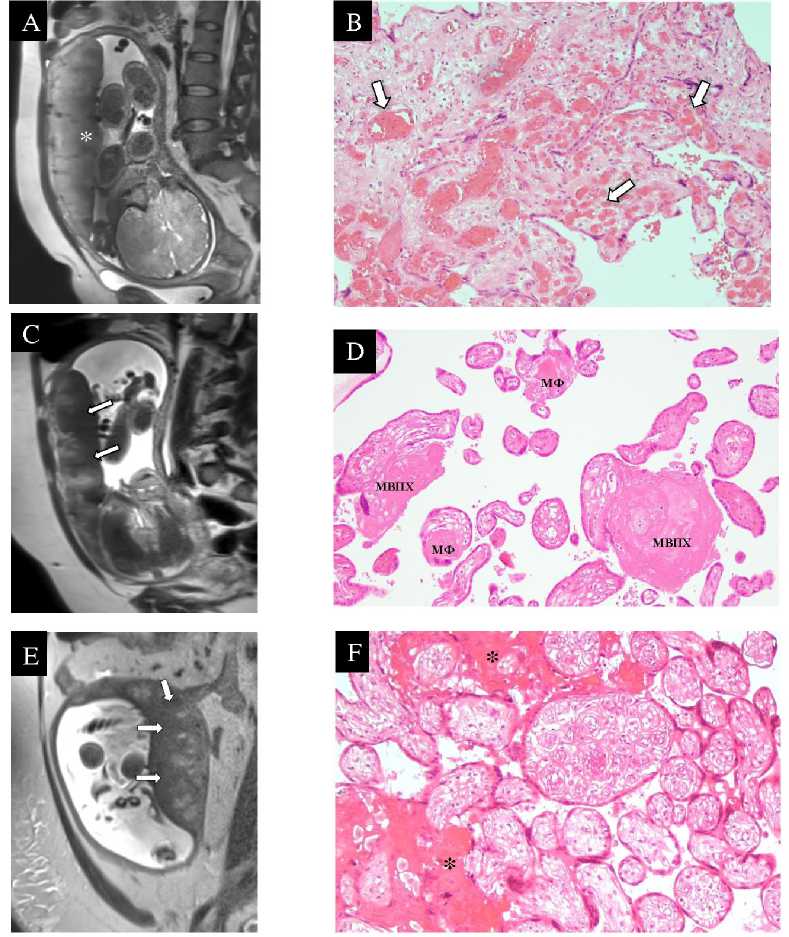

Наиболее характерным МР-признаком в исследуемой группе стало формирование диффузноразлитых зон пониженной интенсивности МР-сигнала на Т2-ВИ по плодовой и/или материнской поверхностям плаценты: изогипоинтенсивных (рис. 1, А) и гипоинтенсивных (рис. 1, В, Д). Указанные зоны также имеют низкий МР-сигнал на ДВИ. При- знак определялся во всех 13 случаях (100%), и его появление может быть связано с формированием следующих изменений: диффузное отложение фибриноида в ворсинах хориона и межворсинчатом пространстве (рис. 1, Г), сужение последнего, в т.ч. на фоне неравномерного кровенаполнения ворсин и хориоангиоза (рис. 1, Б), а также развитие псевдоинфарктов (рис. 1, Е), инфарктов и кровоизлияний в структуре плаценты [9]. Фибриноид представляет собой эозинофильную субстанцию, состоящую из фибрина, фибриногена, плазменных белков и пр., и разделяется на фибриноподобный и матриксный. Первый возникает в результате активности материнских тромбоцитов и активации свертывающей системы крови, а также разрушения клеток трофобласта, второй является продуктом секреции вневорсинчатого трофобласта. Оба мо- гут обнаруживаться при нормально протекающей беременности, выполняя ряд важных функций в плаценте, включая опорную, защитную, транспортную и т.д. [15–17]. Однако увеличение площади отложения фибриноида представляет собой компенсаторную патологическую реакцию на мальперфу-зию и гипоксию плаценты, возникающую как следствие аномальных плацентации, инвазии и ремоделирования спиральных артерий на фоне гипертензивных расстройств [18, 19].

Рисунок 1. Зоны пониженного МР-сигнала в структуре плаценты у пациенток с гипертензивными расстройствами и соответствующие им патологические изменения по данным патоморфологического исследования. A. МРТ плаценты на 39 н.г., Т2-ВИ, аксиальная плоскость, диагноз - хроническая артериальная гипертензия (пациентка № 1). По плодовой поверхности плаценты определяется обширная зона изогипоинтенсивного МР-сигнала (*) с неровными нечеткими контурами. B. Плацента при хронической артериальной гипертензии, 39 н.г., световая микроскопия х200, окраска гематоксилин-эозин (пациентка № 1). Незрелая плацента с избыточно васкуляризованными и полнокровными ворсинами хориона (хориангиоз, черные стрелки) и выраженным сужением межворсинчатого пространства. C. МРТ плаценты на 32 н.г., Т2-ВИ, сагиттальная плоскость, диагноз - умеренная преэклампсия на фоне хронической артериальной гипертензии (пациентка № 7). По плодовой и материнской поверхностям плаценты определяются диффузно-разлитые зоны гипоинтенсивного МР-сигнала (стрелки). D. Плацента при умеренной преэклампсии на фоне хронической артериальной гипертензии, 32 н.г., световая

микроскопия х200, окраска гематоксилин-эозин (пациентка № 7). Фибриноидные отложения в строме ворсин хориона, матриксный фибриноид (МФ), и в межворсинчатом пространстве (МВПФ). E. МРТ плаценты на 29 н.г., Т2-ВИ, сагиттальная плоскость, диагноз – тяжелая преэклампсия на фоне хронической артериальной гипертензии (пациентка № 12). По плодовой и материнской поверхностям плаценты определяются диффузно-разлитые зоны гипоинтенсивного МР-сигнала (стрелки). F. Плацента при тяжелой преэклампсии на фоне хронической артериальной гипертензии, 30 н.г., световая микроскопия х200, окраска гематоксилин-эозин (пациентка № 12). Инволютивно-дистрофические изменения ворсинчатого хориона в виде псевдоинфарктов плаценты (*). Также отмечаются гиповаскуляризация ворсин хориона, склонность к их агглютинации и сужение межворсинчатого пространства

В нашем исследовании интенсивность МР-сигнала от плаценты снижалась с увеличением тяжести диагноза и выраженности патоморфологи-ческих изменений. Для плацент на фоне ХАГ были характерны изогипоинтенсивные зоны или нормальный сигнал от ткани плаценты, а в случаях преэклампсии, в т.ч. на фоне ХАГ, преобладали гипо-интенсивные зоны.

При наличии гипоинтенсивных зон характерной была подчёркнутая дольчатость плаценты (рис. 2), что не встречалось в группе изогипоинтенсивных зон: дольки плаценты визуализировались более отчётливо, были разделены толстыми септами ги-поинтенсивного МР-сигнала.

Дополнительно у 54% пациенток (7 наблюдений) отмечалась мелкозернистость долек (рис. 3). Этот признак отражает формирование мелкоочаговых инфарктов и кровоизлияний в структуре ворсин, участков отложения фибриноида в межворсинчатом пространстве и вдоль самих ворсин, а также диссоциированное созревание ворсин хориона [20].